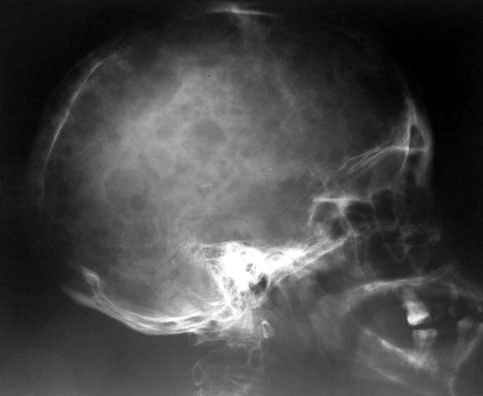

объем изменений совсем не возрастает по направлению к.периферии. В самых редких случаях в какой-то ничтожной

степени в процесс может быть вовлечен череп (часть нижней челюсти). Поражения ребер мы ни разу не наблюдали.